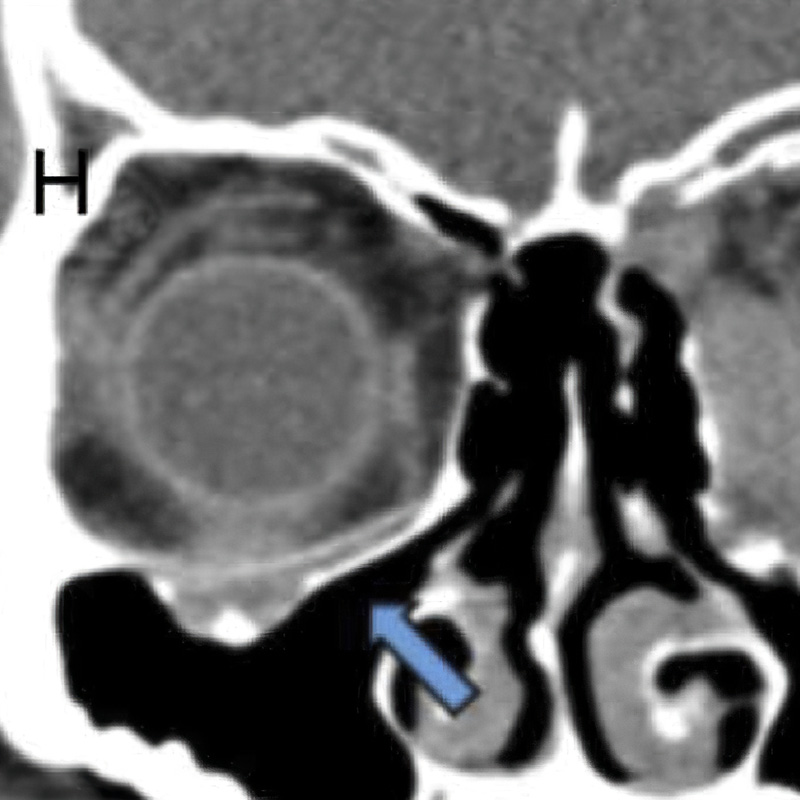

First mandible reconstruction with Osteomesh shaped tray to hold autologous bone grafts. Bony ingrowth and remodeling observed at 2 and 5 months postoperatively.

2019